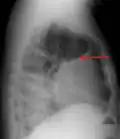

A pleural effusion appears as an area of whiteness on a standard posteroanterior chest X-ray.[15] Normally, the space between the visceral pleura and the parietal pleura cannot be seen. A pleural effusion infiltrates the space between these layers. Because the pleural effusion has a density similar to water, it can be seen on radiographs. Since the effusion has greater density than the rest of the lung, it gravitates towards the lower portions of the pleural cavity. The pleural effusion behaves according to basic fluid dynamics, conforming to the shape of pleural space, which is determined by the lung and chest wall. If the pleural space contains both air and fluid, then an air-fluid level that is horizontal will be present, instead of conforming to the lung space.[16] Chest radiographs in the lateral decubitus position (with the patient lying on the side of the pleural effusion) are more sensitive and can detect as little as 50 mL of fluid. Between 250 and 600mL of fluid must be present before upright chest X-rays can detect a pleural effusion (e.g., blunted costophrenic angles).[17]

A pleural effusion as seen on lateral upright chest x-ray -